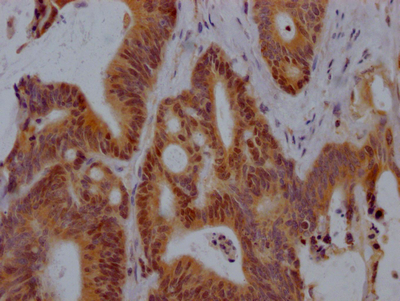

Immunohistochemistry of paraffin-embedded human lung tissue using CSB-PA814217LA01HU at dilution of 1:100